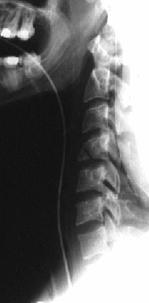

TRAUMA CERVICALA

Incidenta laterala Incidenta

laterala Incidenta

antero-posterioara

Aspect normal Imagine

incompleta Aspect

normal

Incidenta occipitomentala (odontoida)

Aspect normal Incidenta

oblica

Aspect normal

Incidenta oblica Incidenta laterala Incidenta antero-posterioara

Aspect normal Aspect normal Aspect normal